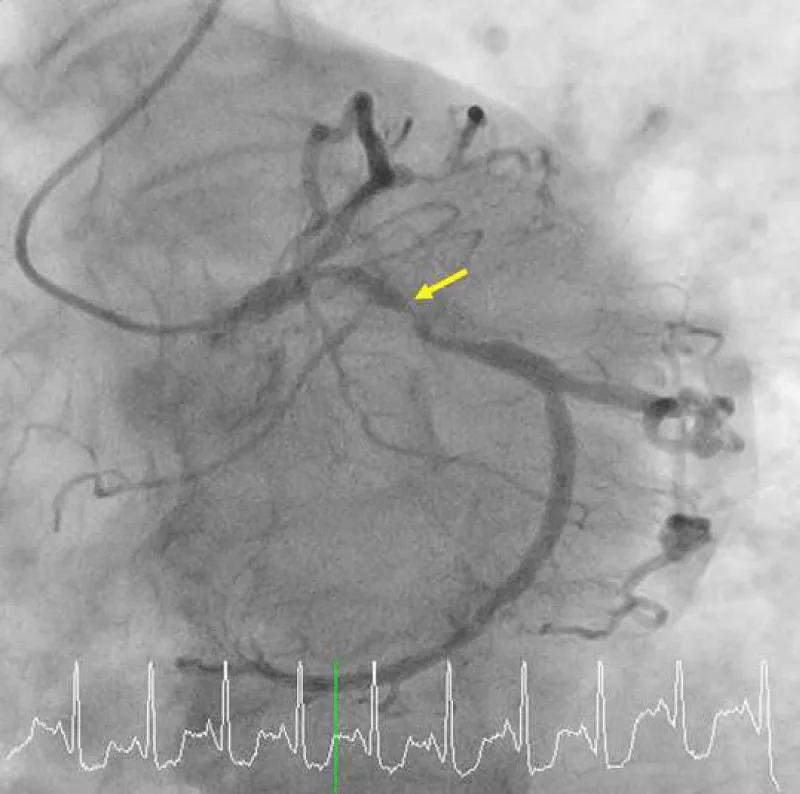

A 75-year-old woman presented with new-onset Canadian Cardiovascular Society Classification Class III angina. A coronary angiogram revealed a 90% blockage of the distal left main trunk (LMT) and a 99% blockage of the ostial left anterior descending coronary artery (LAD) (Video 1A) and (Video 1B). The Syntax Score, Society of Thoracic Surgeons (STS) score and left ventricular ejection fraction (LVEF) were 28, 1.65% and 74%, respectively. A 3.0 × 18-mm CYPHER™ stent had previously been implanted into the dominant proximal circumflex artery (LCx) in 2009 because of unstable angina (Figures 1A,1B). Although some persistent peri-stent contrast staining (PSS) was noted on an angiogram as early as June 8, 2015 (Figure 1C), a single treatment with clopidogrel for antiplatelet therapy was interrupted 7 days before an elective CABG. The patient started complaining of chest pain that corresponded with a marked ST elevation in the inferior posterior leads (Figure 2) and subsequently collapsed on August 7, 2016, in a general ward, 5 days after clopidogrel was discontinued. The patient had a history of dyslipidemia and hypertension but not diabetes, prior cerebrovascular accident, or chronic obstructive pulmonary disease. Her medication included clopidogrel (75 mg), rosuvastatin (2.5 mg), nicorandil (15 mg) and benidipine (8 mg) daily. An emergent bedside echocardiogram showed posteroinferior hypokinesia without any dissection flap in the aortic root (Video 2). Following an aggressive cardiopulmonary resuscitation (CPR) in the general ward, femorofemoral venoarterial extracorporeal membrane oxygenation (VA-ECMO) was inserted in a catheterization laboratory (Video 3). An emergent angiogram revealed a thrombotic stent occlusion of the proximal LCx (Video 4A) and (Video 4B). During angiography, the patient remained pulseless and suffered repeated bouts of ventricular fibrillation, which necessitated defibrillations. When manual aspiration thrombectomy was performed, adequate coronary flow returned instantaneously (Video 5) and (Video 6) and systolic blood pressure improved to 90 mmHg. In the end, an intra-aortic balloon pump was placed and ECMO could be tapered off the same day. The maximum creatine phosphokinase and creatine kinase-MB levels were 4398 and 269 IU/mL, respectively. The following day, the patient underwent on-pump CABG with left internal thoracic artery-LAD and saphenous vein graft-obtuse marginal anastomoses. The patient survived and recovered well without any neurological defect. As of today, LVEF is 55% and single clopidogrel therapy is ongoing. Both bypass grafts and the stent were patent (Video 7).

Figure 1C: Multifocal peri-stent contrast staining is depicted by green arrows, which was observed in 2015. LCx: Left Circumflex; PCI: Percutaneous Coronary Intervention.